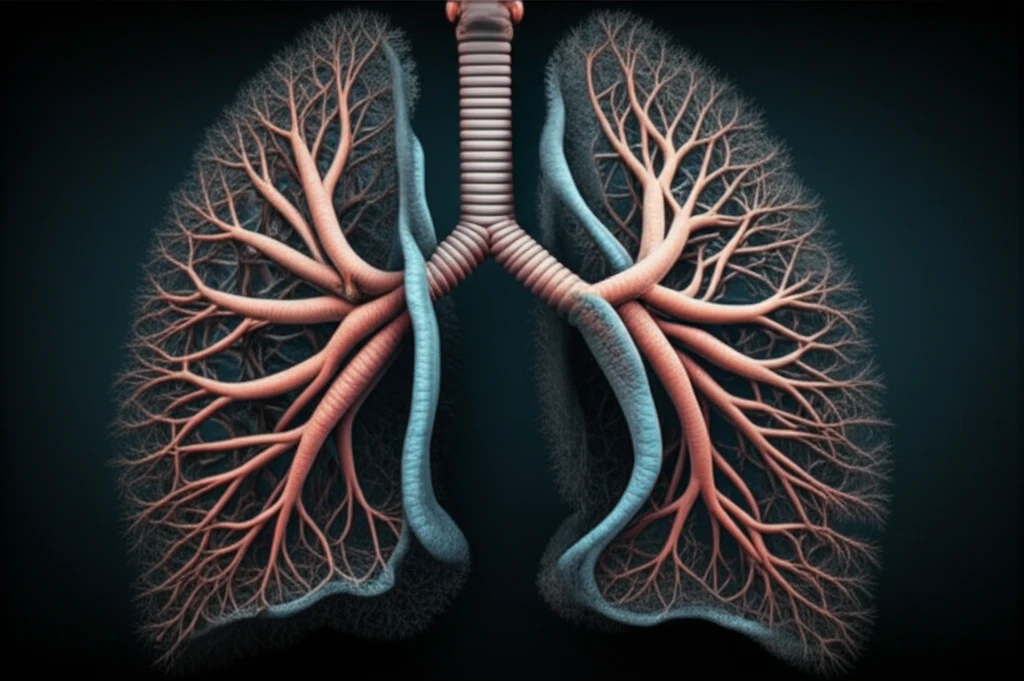

Pneumonia, an infection that inflames the air sacs in one or both lungs, is a serious health concern, especially when it leads to complications or severe illness. The body relies on a complex interplay of immune responses to combat such infections, and scientists are continually working to understand these mechanisms fully.